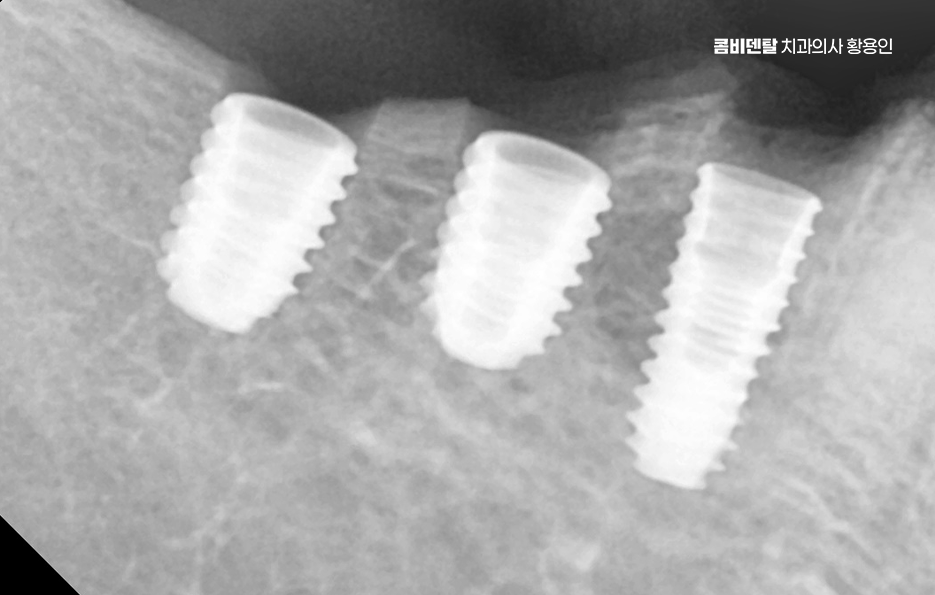

이러한 문제를 막기 위한 효과적인 방법이 바로 임플란트 치료로 어금니 임플란트를 계획할 때는 먼저 잇몸뼈 상태를 정밀하게 확인해야 하며 3D CT 촬영을 통해 뼈의 높이와 두께, 그리고 임플란트를 심을 수 있는 공간을 세밀하게 분석해야 하며 위턱 어금니 같은 경우 상악동이라는 빈 공간이 바로 위에 있어서, 치아가 빠지고 나면 그 공간이 아래로 내려와 임플란트를 심을 자리가 부족해지는 경우가 많고 아래턱 어금니는 하치조신경이라는 중요한 신경이 지나가기 때문에, 신경을 피해서 정확한 위치와 각도로 식립하는 계획이 필요할 수 있어요

어금니는 심미성보다는 저작력을 우선하기 때문에 내구성이 높은 구조로 설계하게 되며 치료가 끝났다고 해서 끝이 아니라, 정기적인 유지관리와 스케일링, 임플란트 주위염 예방을 위한 위생 습관이 반드시 동반돼야 하고 특히 어금니는 입 안 깊숙한 곳에 위치하기 때문에 칫솔질이 어렵고, 음식물이 잘 끼기 때문에 워터픽이나 치간칫솔을 병행해서 관리하는 것이 장기적인 치료 성공과 유지에 있어서 관건이라 할 수 있었어요

결론적으로 어금니 임플란트를 하지 않고 방치하면, 단순히 어금니 하나의 문제가 아니라 전체 교합, 반대편 치아, 나아가 턱관절 기능과 소화 건강까지 영향을 주게 되기 때문에, 가능한 빠르게 치료를 결정하는 것이 장기적으로 더 많은 비용과 시간을 절약하는 방법이 되는 거예요. 특히 뼈가 아직 충분하고, 주변 치아가 건강할 때 임플란트를 진행하면 예후도 좋고, 추가적인 뼈이식이나 부가 수술 없이도 비교적 간단하게 치료가 가능한 경우가 많아서 어금니 상실 후에는 임플란트 치료와의 연계를 잘 고려해서 치료 계획을 늦지 않게 세우시길 바라고 있어요